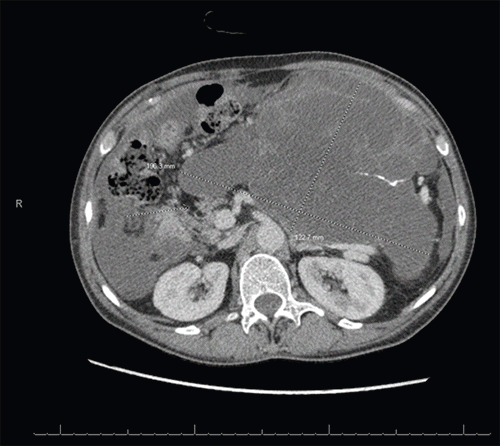

Figure 2. Imaging of Large Multiseptated Pancreatic Cystic Neoplasm with Ascites. Published with Permission

This image reveals the extensive 19.6 cm × 12.3 cm × 13.9 cm multiseptated cystic mass occupying a significant portion of the abdominal cavity. Note the associated mass effect on adjacent organs and the presence of moderate intra-abdominal ascites

A 54-year-old woman with a past medical history of hyperlipidemia and hypothyroidism presented to an outside hospital to evaluate vague symptoms of abdominal pain, bloating, and weight loss for several months. Her initial workup revealed significantly elevated tumor markers: CA 19-9 at 1834 U/mL, CEA at 10.8 ng/mL, and CA 125 at 64.9 U/mL. Computed tomography (CT) of the abdomen and pelvis demonstrated a large 17.7 × 11.2 × 15 cm multiloculated cystic neoplasm with multiple enhancing septations, appearing to replace the pancreatic parenchyma distal to the pancreatic neck. A subsequent positron emission tomography (PET) scan characterized the large pancreatic mass as ametabolic, but noted diffuse fluorodeoxyglucose (FDG) activity within the nodular mesentery.